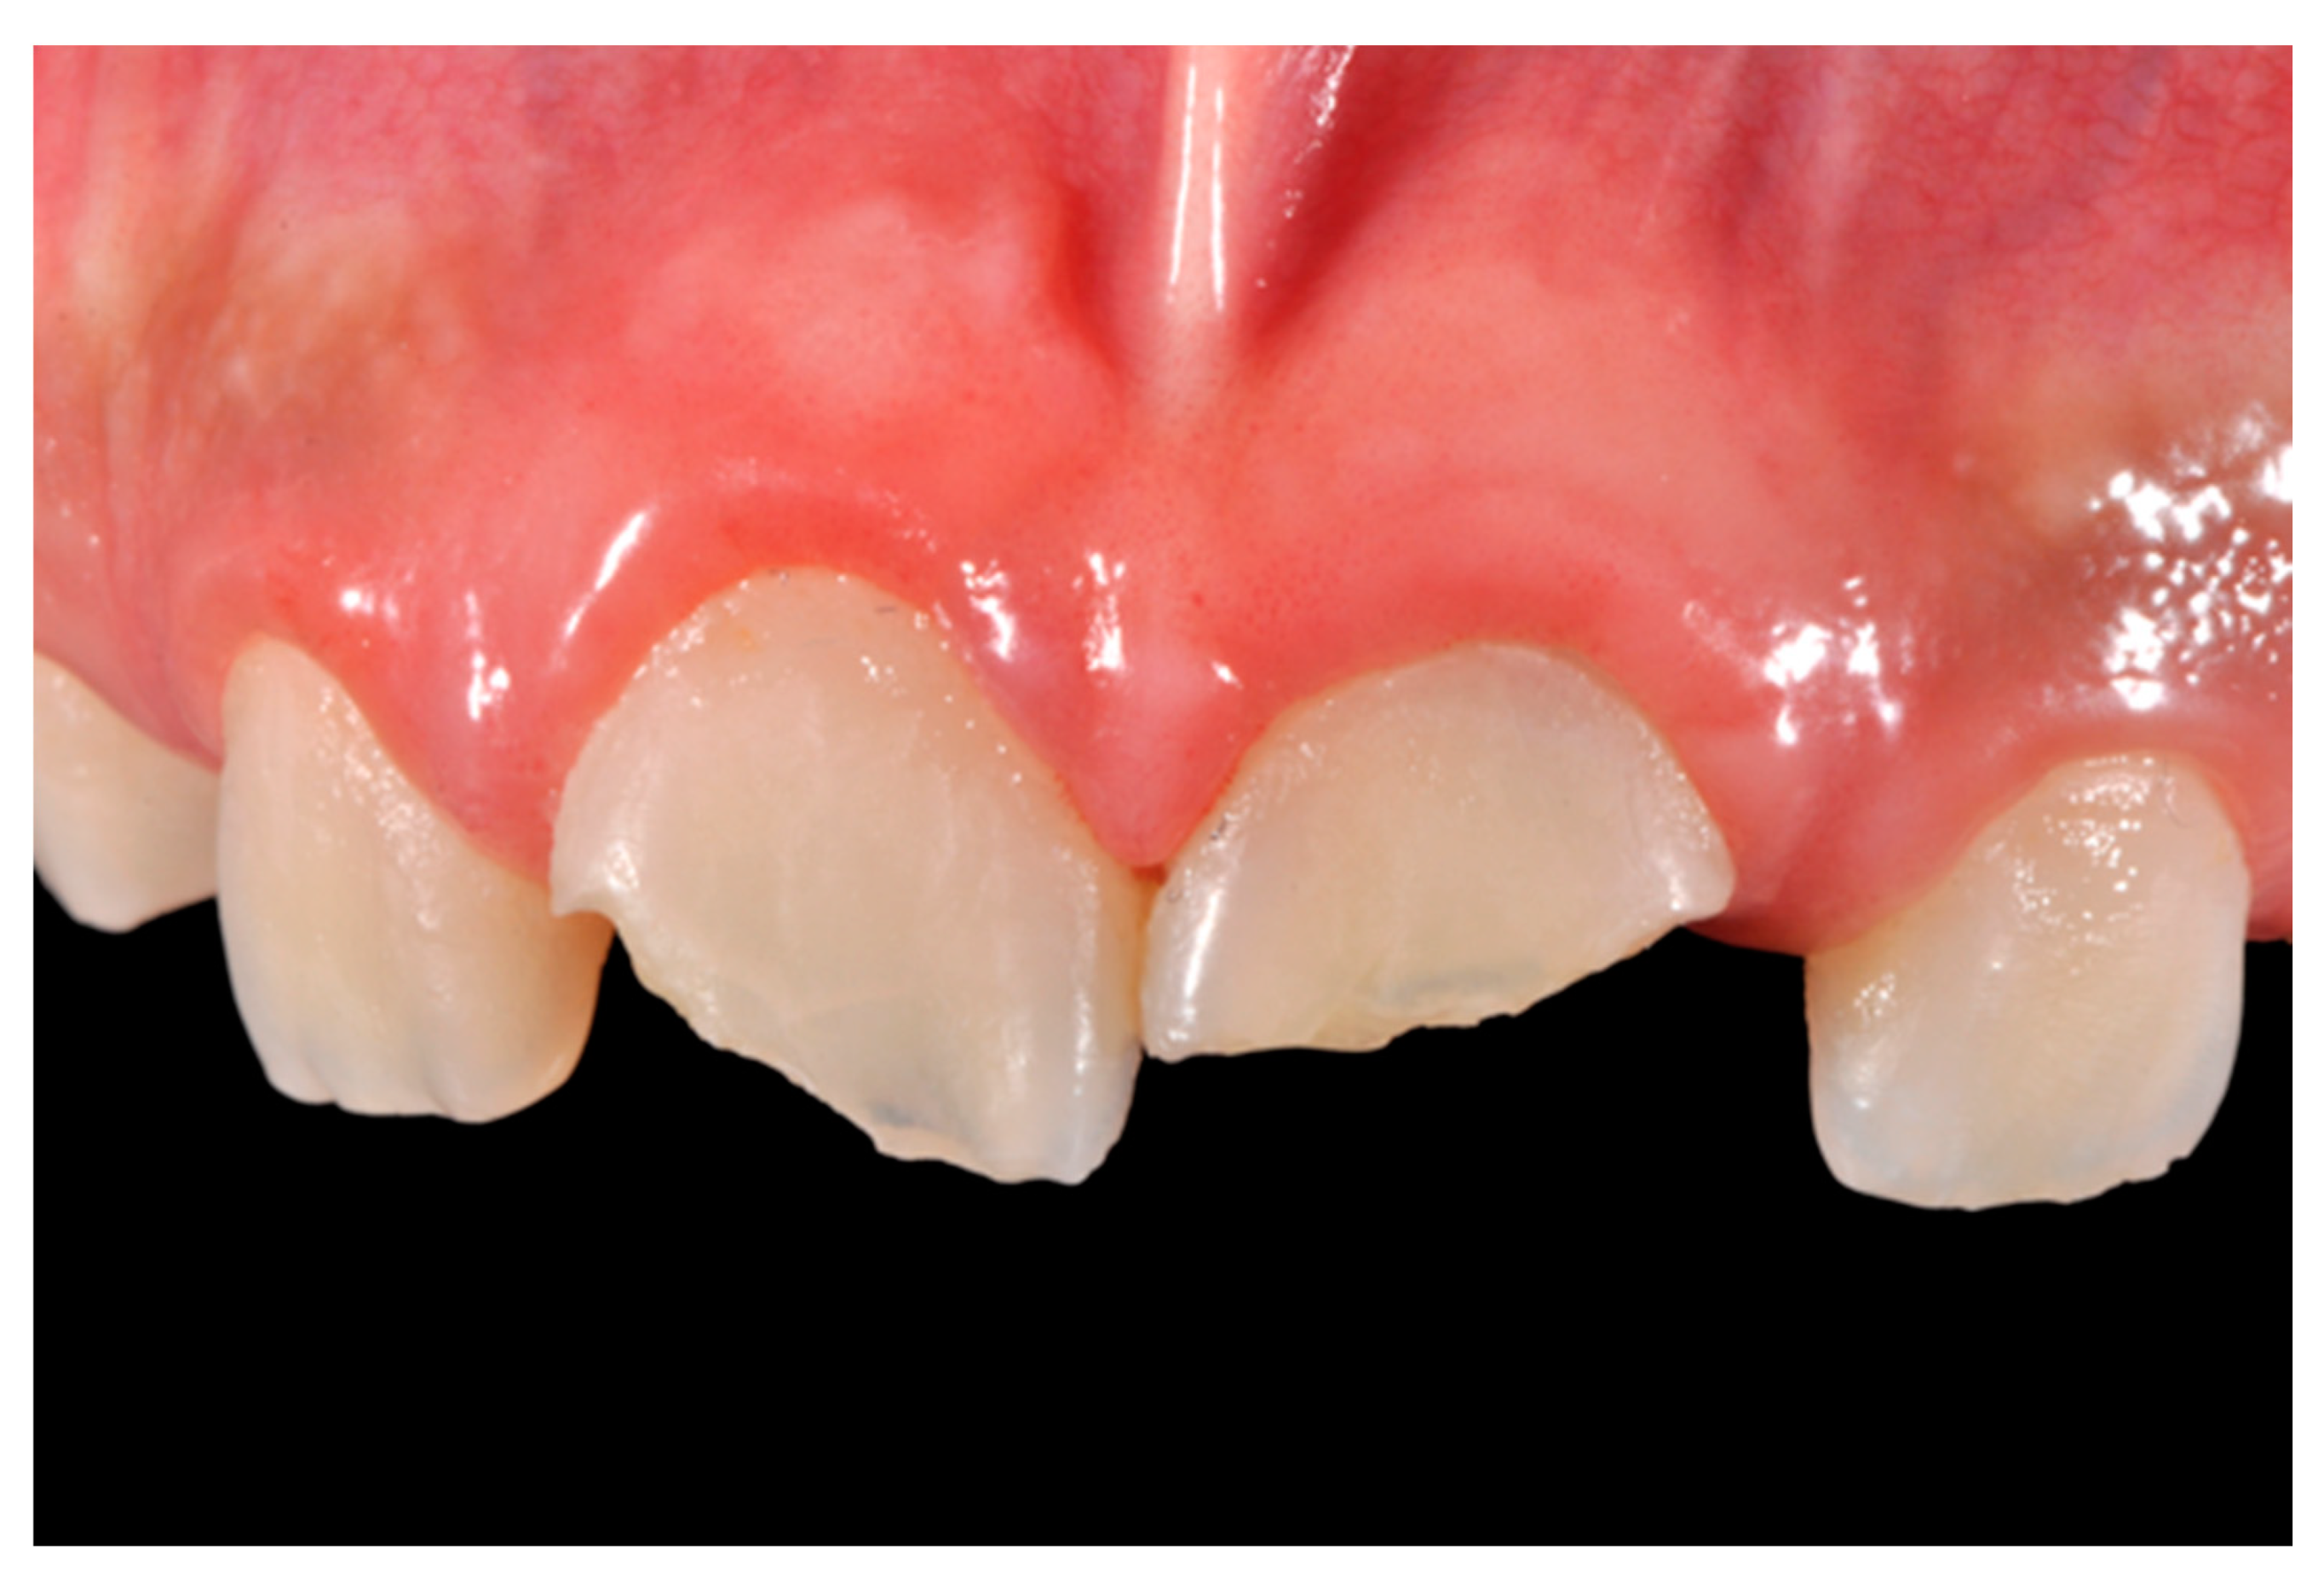

A 27-years lady presented to the dental office after traumatic accident (Figure 30). Tooth #1.1 responded positively to pulp tests (cold and electrical) while Tooth #2.1 showed pulp exposure and continuous bleeding. Endodontic treatment was therefore performed on #2.1 (Figure 31) and direct restoration of both teeth was planned. Shade was selected as described in previous case, using the button-try technique [14]. Even in this clinical case, considered the sufficient ferrule, no post was applied on Tooth #2.1. After isolation and preparation (Figure 32), adhesive procedures were performed using a self-etch two-step adhesive with selective etching procedure (Clearfil SE, Kuraray Noritake Dental, Tokyo, Japan).

Figure 30.

Initial clinical situation. Reprinted from Restauri diretti nei settori anteriori, G. Paolone, S. Scolavino, © 2021, with permission from Quintessence Publishing Italy.

Figure 31.

X-ray after endodontic treatment. Reprinted from Restauri diretti nei settori anteriori, G. Paolone, S. Scolavino, © 2021, with permission from Quintessence Publishing Italy.